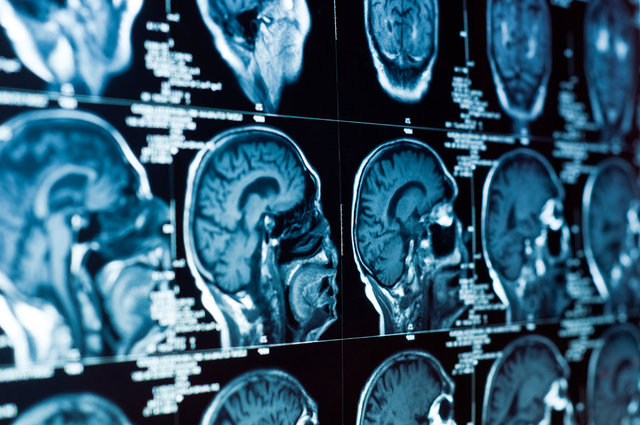

6- Nörolojik bozukluklar: Omurga kırıklarının omurilik kanalına bası yaptığı durumlarda, uzuvlarda his veya güç kaybı ve idrar kaçırma gibi farklı düzeylerde sinir sistemi sorunları görülebilir.